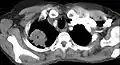

電腦斷層扫描显示一名47岁女性吸烟者患有潘科斯特肿瘤(标记P處:非小细胞肺癌,右肺)

通常在评估临床症状與影像學檢查後可诊断之。胸部X光是不錯的初步檢查,但胸部電腦斷層掃瞄可以提供更好的解析度與判斷對內臟的影響。